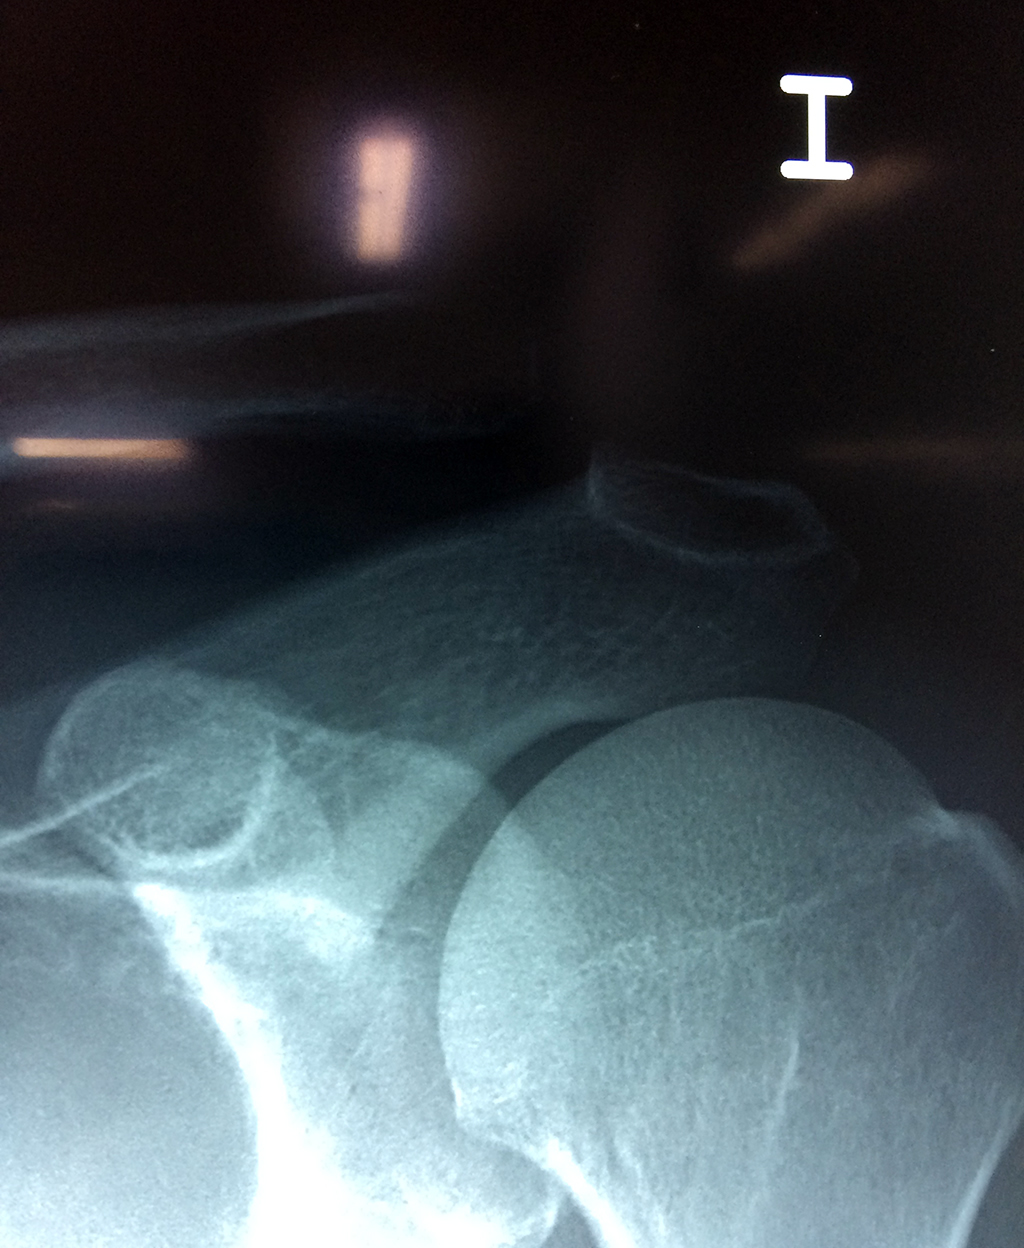

Cirugías de Codos - Clavícula

Se considera el único medio de unión entre el miembro superior y el tórax. A pesar de su aspecto, similar al de un hueso largo, posee una estructura semejante a la de un hueso plano, ya que carece de epífisis y de diáfisis, lo que la harían entrar dentro de la clasificación de hueso largo. Carece de un canal medular propiamente dicho.